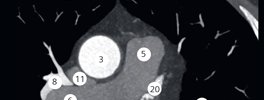

CT Cardiac Anatomy